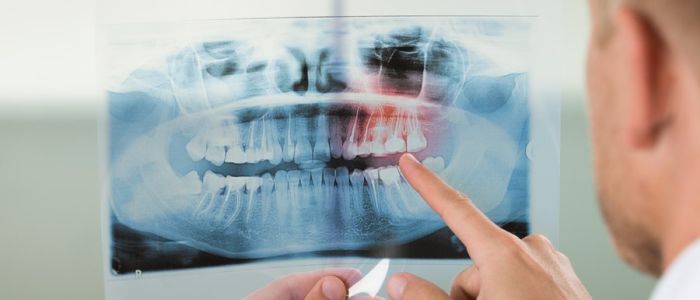

Radiografías Intraorales

Son aquellas en las que la película se coloca en el interior de la cavidad bucal. Según el tamaño y la colocación de la película se pueden clasificar en procedimientos periapicales o retroalveolares o retroalveolares, bite wing o interproximales y oclusales.